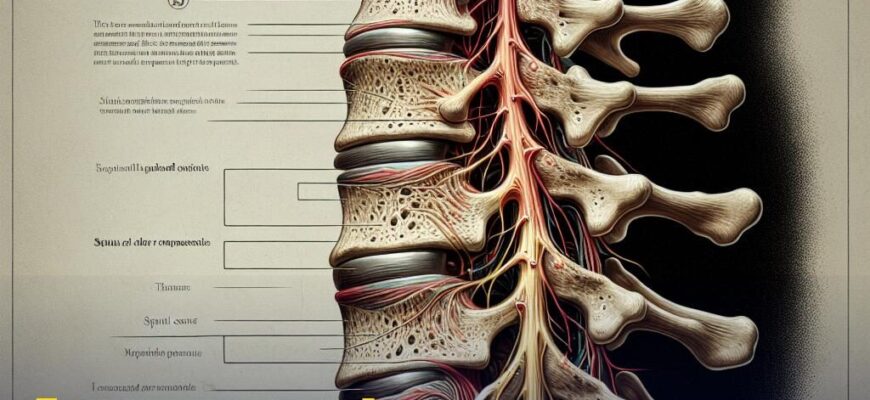

Що викликає спазми м’язів спини?

Іноді це банальне перевантаження або недолік фізичної активності. Як виявляється, навіть тривале сидіння на стільці може стати причиною проблем. Стрес та смикання нервів ще більше ускладнюють ситуацію. Чому спина так любить робити нам капості? Це справжня загадка.